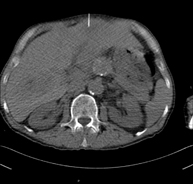

Prova diagnòstica que consisteix en l'estudi de l'abdomen d'alta definició anatòmica (fetge, vesícula biliar, via biliar, pàncrees, melsa, estómac, intestins, ronyons, estructures vasculars, bufeta, úter i ovaris, etc.) mitjançant l'ús d'un equip de TC (Tomografia Computeritzada). Aquestes imatges s'estudien posteriorment en una estació de treball que permet obtenir reconstruccions bidimensionals en diferents plànols de l'espai i també reconstruccions 3D (volumètriques). La majoria d'estudis requereixen l'ús de contrast iodat per millorar la definició de les imatges. - TC Pelvis

Prova diagnòstica que consisteix en obtenir imatges bi i tridimensionals de l'abdomen d'alta definició anatòmica (estructures òssies, estructures vasculars, fetge, pàncrees, vesícula biliar, ronyons, glàndules suprarenals, melsa, intestí prim i gros, bufeta, úter i ovaris, pròstata i vesícules seminals, urèters, etc.) mitjançant l'ús d'un equip de TC (Tomografia Computeritzada). La majoria d'estudis requereixen l'ús de contrast iodat. - TC Fetge